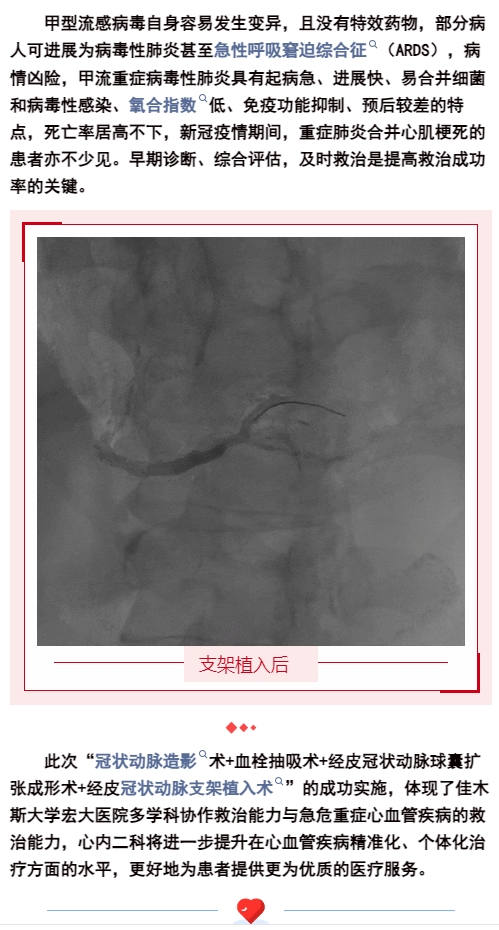

生死時(shí)速,為“心”護(hù)航,為患者打開生命之門!【佳木斯大學(xué)宏大醫(yī)院】